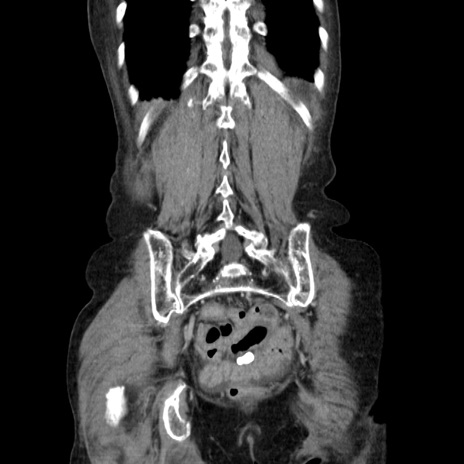

症例25(冠状断像)

症例

【症例】80歳代女性

【主訴】胸のつかえ感

【現病歴】約9時間前に食後から胸のつかえた感じあり、嘔吐あり、来院。

【既往歴】胃癌(全摘)、胆摘、虫垂炎

【身体所見】心窩部に圧痛あり、反跳痛なし。

【データ】WBC 5700、CRP 0.05